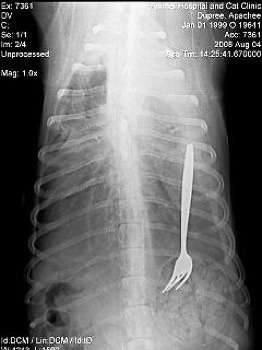

![]() |

| Một con chó ở bang North Carolina với cái dĩa trong ổ bụng. |